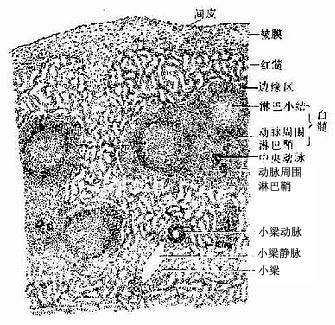

1.脾的结构脾内也含有大量淋巴组织,但其淋巴组织的分布规律与淋巴结不同。脾无皮质髓质之分,而分为白髓、边缘区和红髓三部分;脾内无淋巴窦,但有大量的血窦(图9-18)

图9-18 脾

(1)被膜与小梁:脾的被膜较厚,表面覆有间皮,被膜结缔组织伸入脾内形成许多分支的小梁,它们与门部分支形成的小梁相互连接构成一粗的支架。被膜和小梁内含有许多散在的平滑肌细胞,其收缩可调节脾内的血量,小梁之间的网状组织构成脾淋巴组织的微细支架。

(2)白髓(white pulp):主要由淋巴细胞密集的淋巴组织构成,在新鲜脾的切面上呈分散的灰白色小点状,故称白髓。它又要分为动脉周围淋巴鞘和淋巴小结两部分。

动脉周围淋巴鞘(periarterial lymphatic sheath):是围绕在中央动脉(central antery)周围的厚弥散淋巴组织(图9-18,9-19),由大量T细胞和少量巨噬细胞与交错突细胞等构成。此区相当于淋巴结内的副皮质区,是胸腺依赖区,但无高内皮毛细管后微静脉。中央动脉旁有一条伴行的小淋巴管,它是鞘内T细胞经淋巴迁出脾的重要通道(图9-19)。当发生细胞免疫应答时,动脉周围淋巴鞘内的T细胞分裂增殖,鞘也增厚。

淋巴小结:又称脾小体(splenic corpuscle),结构与淋巴结的淋巴小结相同,主要由大量B细胞构成,发育较大的淋巴小结也呈现生发中心的明区与暗区,帽部朝向红髓(图9-19)。健康人脾内淋巴小结很少。当抗原侵入脾内引起体液免疫应答时,淋巴小结大量增多,它出现于边缘区和动脉周围淋巴鞘之间,使中央动脉常偏向鞘的一侧。

(3)边缘区(marginal zone):位于白髓和红髓交界处,宽约100μm。该区的淋巴细胞较白髓稀疏,但较脾索密集,并混有少量红细胞。此区含有T细胞及B细胞,并含有较多的巨噬细胞。从肌髓或胸腺迁入脾的处女型淋巴细胞常先聚集于此区继续成熟。中央脉侧支分支而成的一些毛细血管,其末端在白髓和边缘区之间膨大形成的小血窦,称为边缘窦(marginal sinus),它是血液以及淋巴细胞进入淋巴组织的重要通道,淋巴细胞也可经此区再迁入动脉周围淋巴鞘、淋巴小结或脾索内。边缘区也是脾内捕获抗原、识别抗原和诱发免疫应答的重要部位,它相当于淋巴结浅层皮质与副皮质的交界处。

(4)红髓(red pulp):约占脾衬质的2/3,分布于被膜下、小梁周围及边缘区外侧,因含有大量血细胞,在新鲜脾切面上呈现红色。红髓由脾索及血窦组成(图9-20)。